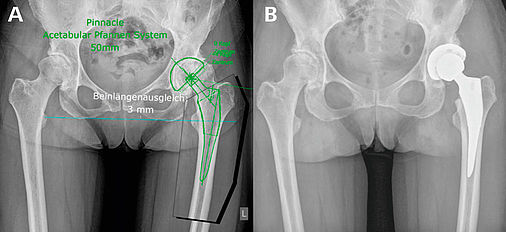

Эндопротезирование тазобедренного сустава: фото и схемы

Раздел: Необычные решения